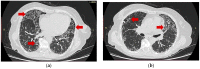

The current study aimed to evaluate rheumatoid arthritis (RA) patients with interstitial lung disease (ILD) in clinical practice and whether disease characteristics are associated with X-ray and high-resolution computed tomography (HR-CT) findings. Medical history of RA patients from a tertiary rheumatology clinic was retrieved from its electronic database starting from 1 January 2019 until the study date (8 August 2022) using International Classification of Disease version 10 codes for RA, ILD and exclusion criteria. The study included 78 RA patients (75.6% women, 15.4% active smokers), with average time from RA to ILD of 5.6 years. Regarding chest X-ray findings, men had a higher prevalence of nodules, combined fibrosis and nodules and combined bronchiectasis and nodules, rheumatoid factor (RF)-positive patients had a higher prevalence of fibrosis and anti-cyclic citrullinated peptide antibodies (ACPA)-positive patients had a higher prevalence of bronchiectasis. Regarding HR-CT findings, patients actively treated with methotrexate had a higher prevalence of nodules; a combination of fibrosis and nodules; combination of emphysema and nodules; and combination of fibrosis, emphysema and nodules. ILD develops within approximately 5 years from RA diagnosis, and ILD-associated imaging findings on chest X-rays and HR-CT are more prevalent among men with RA, among patients with positive RA serology (RF and/or ACPA) and RA patients on methotrexate.